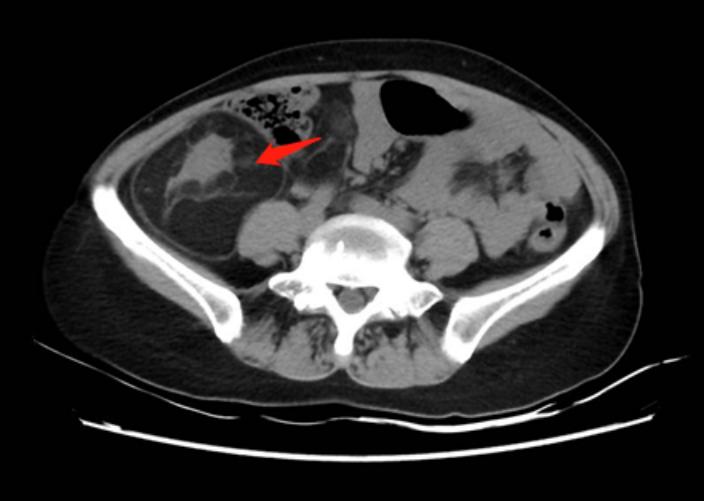

辅助检查:我院腹部CT(肿物最大直径处截图)。

2019年11月04日我院腹部CT复查:1.脂肪肉瘤术后改变,考虑右中下腹膜后肿瘤复发,较前进展(55mm×54mm);考虑肝肾间隙及肝右叶外缘新见多发转移灶(17mm×15mm)。2、胆道积气,胆道感染待排;考虑肝S4小囊肿,肝S5肝内胆管小结石,胆囊小结石,右肾小囊肿,同前。3、.胸腰椎退行性变。4、胸部CT检查未见明显异常。

2020年6月17日腹部CT复查:1、符合脂肪肉瘤术后改变,考虑右中下腹膜后肿瘤复发,较前进展(72mm×74mm,前片约55mm×54mm);考虑肝肾间隙及肝右叶外缘转移灶,部分较前进展(17mm×15mm),右肾后间隙新发转移灶(直径14mm,前片约10mm)。2、胆道积气,请结合临床;考虑肝S4小囊肿,肝S7/8段交界区血管瘤。肝S5肝内胆管小结石,胆囊小结石,右肾小囊肿,同前。十二指肠球部溃疡可能,局部粘膜连续性欠佳,请结合临床,建议内镜检查。3、右中肺及双下肺少许纤维灶。主动脉硬化。升主动脉瘤样扩张。